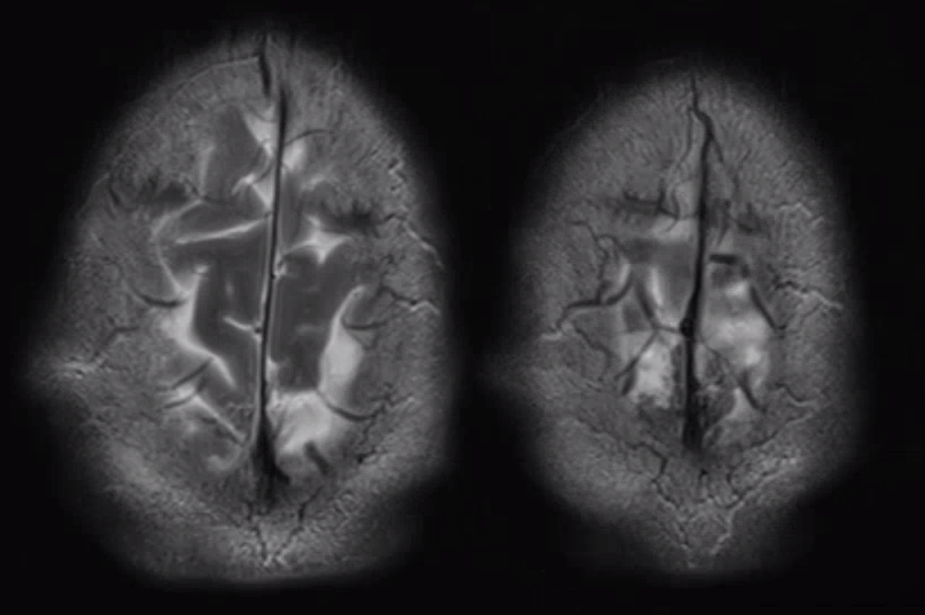

Another compensation for hypoplasia of the SSS is shift of superficial drainage into the deep venous system via the medullary veins draining into the internal cerebral veins. Courtesy Dr. Gopi Nayak. There is hypoplasia of the Superior Sagittal Sinus.

As one way of compensation for this superficial venous system deficiency, there is more venous drainage routed to the deep system. Amazing images of deep medullary/transverse venous prominence — completely nonpathologic, simply reflecting a shift of drainage equilibrium towards the deep venous system

Some arrows. Open white arrows — septal veins on the medial aspect of frontal horn. Thick white arrows — longitudinal caudate venous arcade. Black arrow — direct lateral vein, prominent because of hypoplasia of the posterior segment of the left longitudinal caudate vein. Thin white arrows are transverse/ medullary veins

Here is a diagrammatic way of showing the same thing